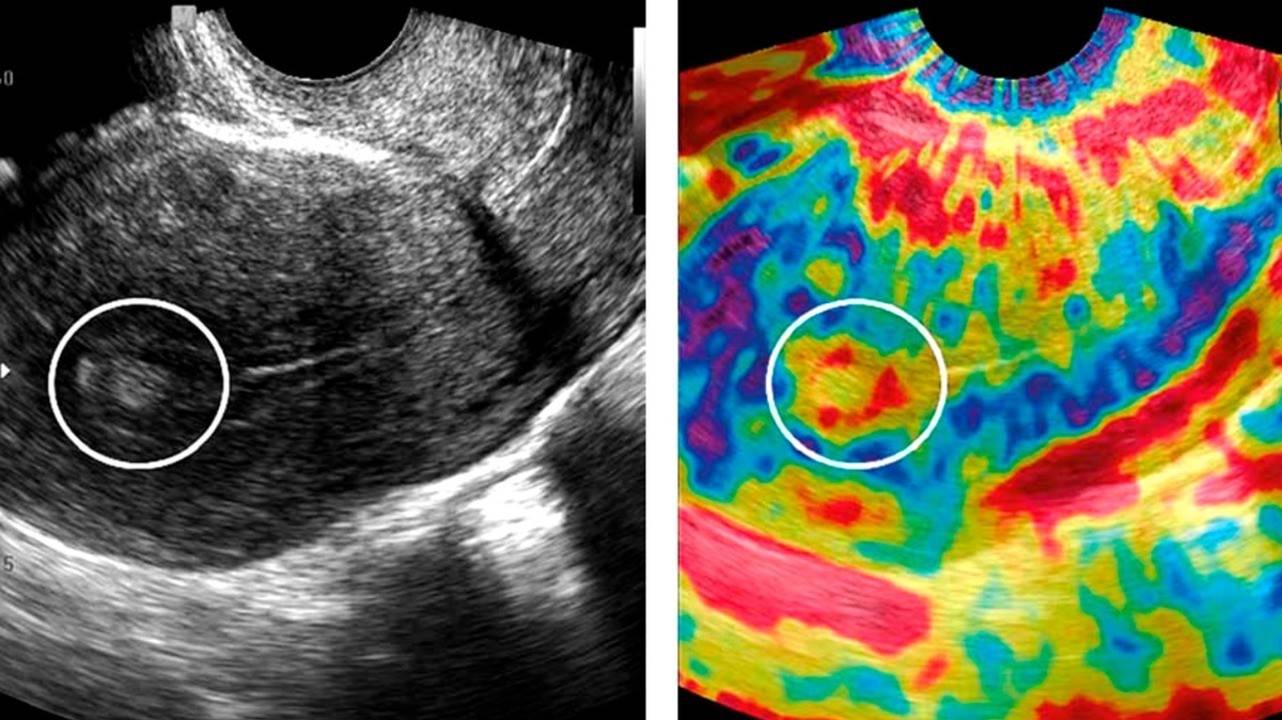

Полипы на снимке УЗИ. Фото: Prz Menopauzalny / Open-i (CC BY-NC-ND 3.0)

В нашей Клинике проведено комплексное клинико-лабораторное обследование. В результате обследования ВЫЯВЛЕН плацентарный ПОЛИП (фрагмент плацентарной ткани) 11*5 мм, расположенный на задней стенке в средней трети полости матки, с сосудистой ножкой (см. фото 1).

Плацентарный полип возникает вследствие неполного отторжения плаценты (детского места). Наличие сосудистой ножки свидетельствует о достаточном питании данного участка ткани и малой вероятности его самостоятельного отторжения. Однако наличие фрагмента плаценты не позволяет матке полностью сократиться и поддерживает вялотекущий ВОСПАЛИТЕЛЬНЫЙ ПРОЦЕСС в полости матки.

В асептических (безмикробных) условиях под ультразвуковым контролем без расширения канала шейки матки выполнена прицельная пайпель-биопсия плацентарного полипа.

Возможность ультразвукового контроля в Курортной клинике женского здоровья значительно расширяет лечебно-диагностические возможности, позволяя УДАЛИТЬ непосредственно полип БЕЗ ТРАВМАТИЗАЦИИ окружающих тканей.